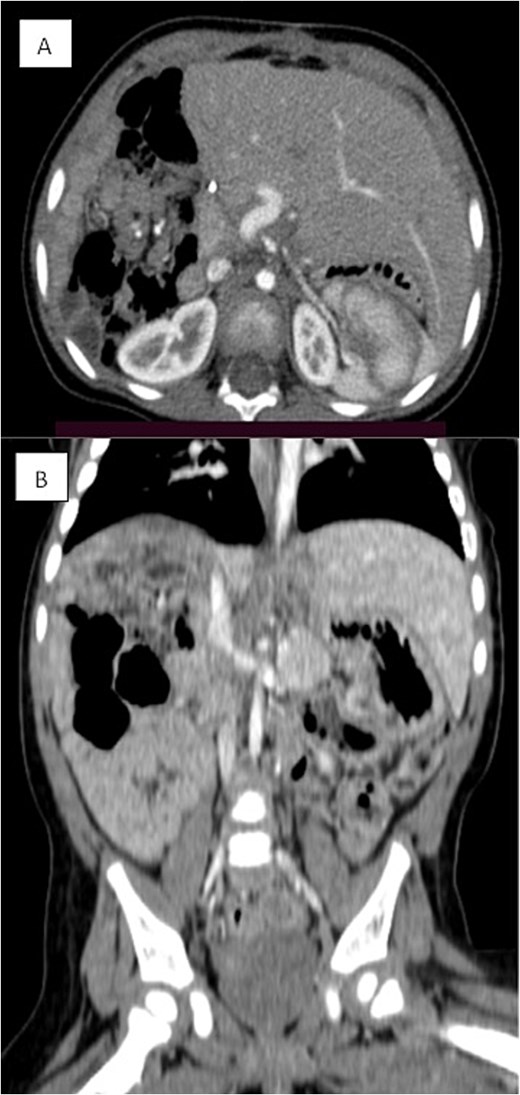

Several months later, she developed progressive abdominal distension and recurrent vomiting, prompting further evaluation. A CT scan of the abdomen revealed a large heterogeneous hepatic mass primarily occupying the right lobe, measuring 12.6 × 8.8 × 14 cm, with multicystic areas and soft tissue enhancement. MRI also demonstrated a large right hepatic lobe mass with mass effect and heterogeneous enhancement (Figs 1 and 2). Mild upper abdominal lymphadenopathy was noted (largest node 8 × 10 mm), along with a right-sided inguinal hernia. Differential diagnoses included HMH, with hepatoblastoma and undifferentiated sarcoma considered less likely. A chest CT showed mild pericardial effusion and an inflammatory appearance.

Coronal MRI images of the abdomen showing a mass effect in the right hepatic lobe. (A) Coronal T1 post-contrast and (B) coronal T2 HASTE FS images demonstrate spatial relationships, including compression of the right kidney, pancreas, and major vessels, with no invasion. The mass displaces bowel loops inferiorly and causes an anterior abdominal wall bulge.

Dynamic MRI of the abdomen demonstrating a large, partially cystic, and solid lesion arising from the right hepatic lobe. (A) Axial T1 and (B) axial T2 images show the lesion’s mixed composition and internal structure. (C) Arterial and (D) portovenous phase post-contrast images reveal heterogeneous enhancement of the solid and septal components.